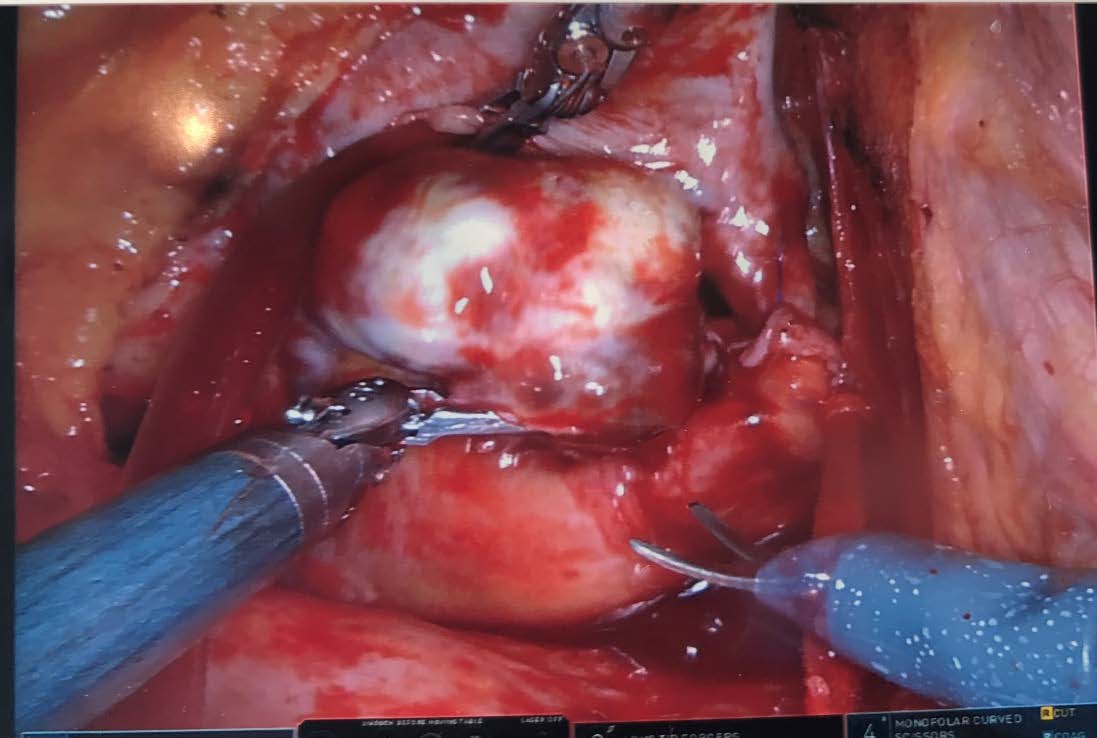

In September 2018, approximately 9 months after initial presentation, the patient underwent surgical removal of the atrial myxoma near the interatrial septum proximate to the venous septum and right atrial junction via minimally invasive thoracic robotic surgery (Figure 2). A large egg- to peach-sized mass was sent for pathology testing, the results of which confirmed the diagnosis of benign atrial myxoma with fibrosis, calcification, and ossification (Figure 3).

Figure 2. Right atrial myxoma located intraoperatively near the venous septum and right atrial junction.

Figure 3. Right atrial myxoma, described as the size of a small peach by the cardiothoracic surgeon.